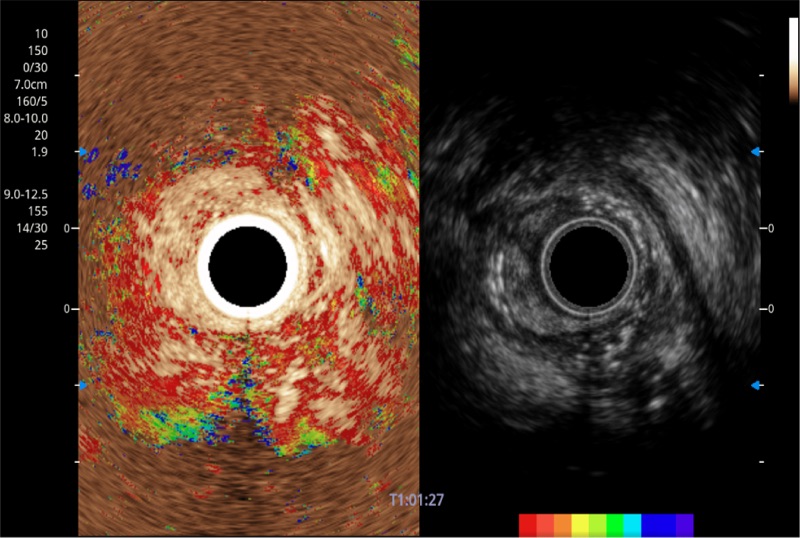

可人为将灰阶图像转变成彩色的显示方式,增强人眼对于不同回声强度的敏感度,主观上增加了图像分辨率

微米成像技术提升了对组织斑点噪声信号的抑制能力,并进一步强化边界信息,从而获得信噪比更优、边界更清楚锐利的图像